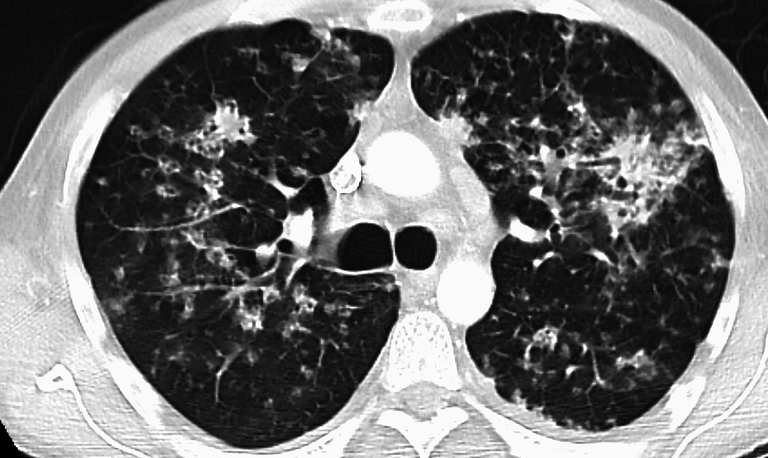

Pulmonary TB BY James Heilman - CC BY 3.0, link

1. Pulmonary tuberculosis

A quick look at the onset of the illness shows that the bacteria causing the disease attacks the lungs causing what is known as a Pulmonary TB. It is a form of tuberculosis that involves the lung parenchyma (tissues) and is characterized by lesions in the lungs. As stated before, it's symptoms are coughing for more than two weeks, coughing out sputum/blood, pain in the chest when breathing or coughing. However, constitutional symptoms that can develop are loss of appetite, fever, weight loss, night sweats and tiredness.